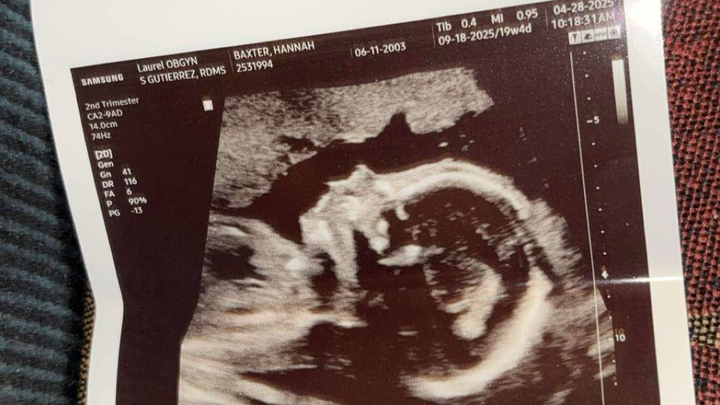

This past Monday, I went to the OB for my 20-week ultrasound with a mix of excitement and anxiety. After experiencing a miscarriage last year, I had no idea what to expect, but I tried to keep a positive mindset, especially since I was about to see my beautiful baby. The ultrasound tech was amazing, explaining everything and reassuring me that things looked great—until she said something I never imagined I’d hear.

She gently asked, “Do you remember what your daughter’s ultrasound looked like?” I replied, “Kinda, not really, haha.” Then, I sensed something was off. She paused and said, “I’m so sorry to tell you this, but your baby has only the right side of her heart. It’s called hypoplastic left heart syndrome.”